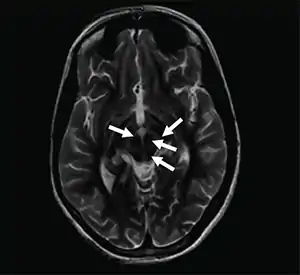

| Axial T2-weighted MRI of the brain at the level of the midbrain showing the characteristic ‘face of the giant panda’ sign, with normal red nuclei and substantia nigra (pars reticulata) against a background of hyperintensity in the tegmentum, as well as hypointensity of the superior colliculi | |

The face of the giant panda sign, panda sign of the midbrain or double-panda sign is a characteristic "panda's face" appearance in magnetic resonance imaging (MRI) images of people with Wilson's disease. Along with Kayser–Fleischer rings, the sign is helpful in diagnosis.[1]

While the sign is most common in Wilson's disease, it has been rarely reported in acute disseminated encephalomyelitis,[2] rabies encephalopathy,[3] toxic leukoencephalopathy[4] and Leigh syndrome.[5]